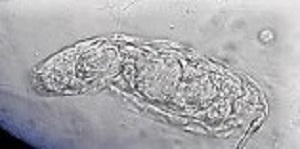

A 10-year-old female patient from Argentina was taken to the hospital by her parent with complaints of “not feeling well.” A urine sample was collected and examined as part of the routine checkup. Microscopic examination of the urine sediment using the 40x objective lens revealed the following: 0-1 WBC and 0-2 RBC per field and a motile organism shown in the video that was sent to the DPDx team for identification. Still images of the organism were made by capturing screenshots at different points of the video (Figures A – C). What is your diagnosis? Based on what criteria?

Figure B